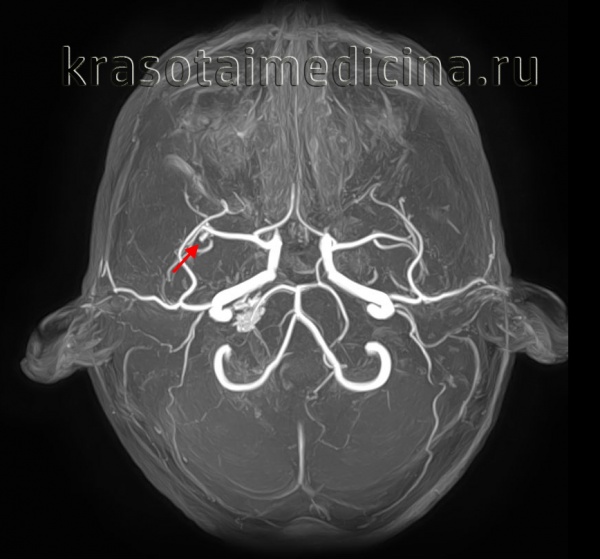

КТ-ангиография головного мозга (3D-реконструкция). Аневризматическое расширение левой средней мозговой артерии

- Ангиографию. Церебральная ангиография позволяет установить расположение, форму и размеры аневризмы. В отличие от рентгенологической ангиографии магнитно-резонансная (МРА) не требует введения контрастных веществ и может проводиться даже в остром периоде разрыва аневризмы сосудов головного мозга. Она дает двухмерное изображение поперечного сечения сосудов или их объемное трехмерное изображение.

При торпидном течении АВМ МРТ и КТ головного мозга могут оставаться в норме. Обнаружить сосудистую мальформацию в таких случаях позволяет лишь церебральная ангиография и ее современные аналоги — КТ сосудов и МР-ангиография. Исследования церебральных сосудов проводятся с использованием контрастных веществ. Диагностика осуществляется нейрохирургом, который также оценивает операционный риск и целесообразность хирургического лечения АВМ. При этом следует учитывать, что при разрыве, в связи с компрессией сосудов в условиях гематомы и отека мозга, томографический размер АВМ может быть существенно меньше реального.